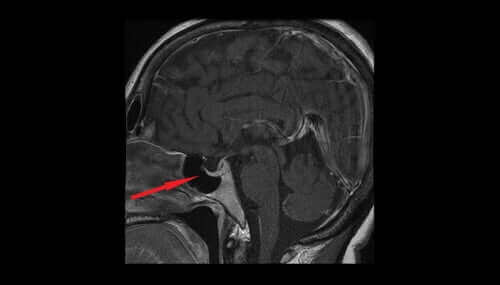

Vasopressiini, joka tunnetaan myös antidiureettisena hormonina (ADH), erittyy hypotalamuksen magnosellulaarisista tumakkeista, joista se kulkeutuu neurohypofyysiin eli aivolisäkkeen takalohkoon ja lopulta verenkiertoon. Se auttaa säätelemään nesteen määrää elimistössä kontrolloimalla munuaisten erittämän nesteen määrää. Tässä artikkelissa käymme läpi vasopressiinin ominaisuudet ja vaikutukset.